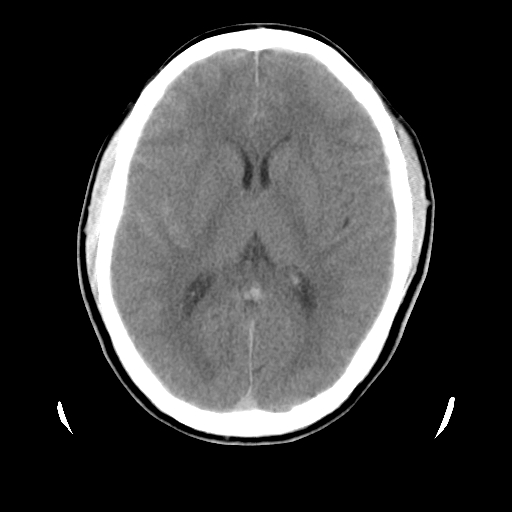

男,51岁,头外伤一小时,呕吐两次。

蛛网膜下腔出血 脑肿胀

左侧颞部硬膜外;蛛网膜下腔出血 ;脑肿胀

1)左侧中颅窝蝶骨翼后方硬膜外血肿。2)左侧颞顶部硬膜下血肿。3)蛛网膜下腔出血。4)左侧筛窦及双侧蝶窦炎症(或积血)。5)左侧额部头皮软组织肿胀。

蛛网膜下腔出血

左侧硬膜外 下血肿  硬膜下血肿影不出外是蛛网膜下腔出血

左颞顶不头皮血肿,左侧颞不硬膜(下)血肿,蛛网膜下腔出血

1:左侧硬膜外及硬膜下混合血肿。2:蛛网膜下腔出血。3:左额部少量颅内积气?

左颞部硬膜外血肿,蛛网膜下腔出血,副鼻窦积液.头皮损伤.